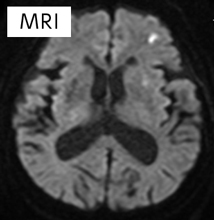

97歳女性、脳主幹動脈閉塞による脳梗塞

意識障害、右半身麻痺にて発症し、救急車にて来院。

3DCTAngiographyにて左内頸動脈閉塞を認める(矢印)。

血栓回収療法を施行

①左内頸動脈が閉塞している(矢印)。

②ステント型血栓回収機器を用いて血栓を回収(矢印)。

③血管が再開通している

④ステント型血栓回収機器と回収された血栓

MRIにて脳梗塞は小さい範囲となっていることを確認。

術直後より意識清明となり、麻痺は改善した。